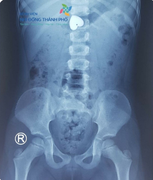

Khi đang cầm mặt dây chuyền hình trái tim chơi, bé gái 4 tuổi ở Sóc Trăng vô tình nuốt luôn vào bụng.